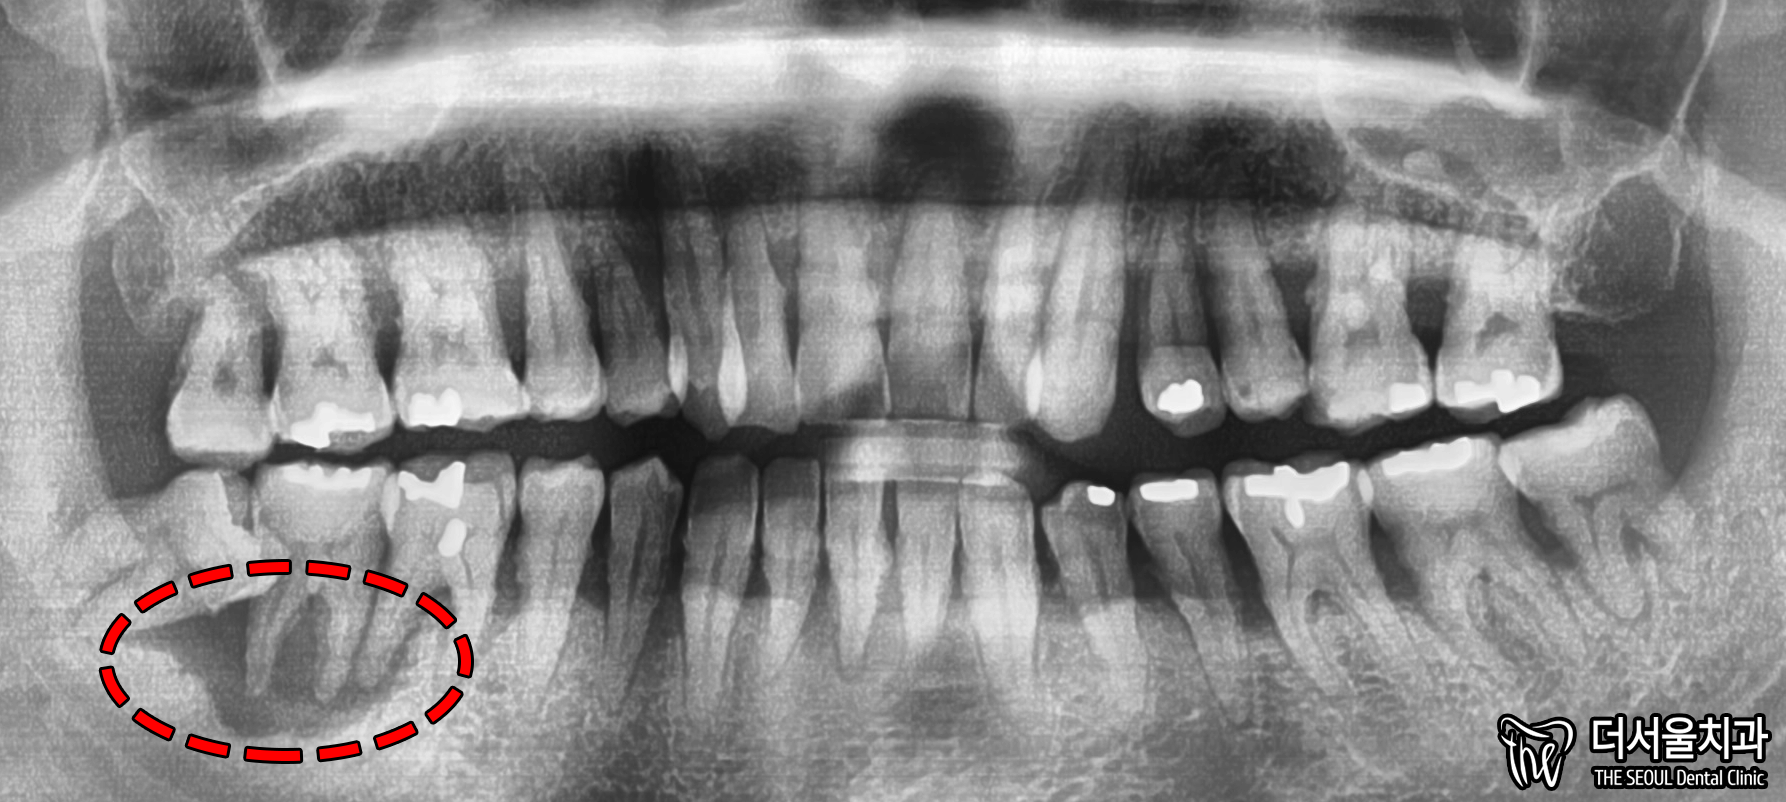

먼저 사진을 보겠습니다.

여러분이 보더라도

구강 상태가 심각하다는 걸 알 수 있습니다.

올바른 교합이 이뤄질 수 없을 뿐더러

치경부 마모증에 쌓여있는 치석에 충치까지

손댈 부분이 너무 많네요.

게다가 구취까지 나고 있었기에

걱정되는 상황이었습니다.

교합면을 확인했을 때도 마찬가집니다.

인접면에 있는 충치와

누워있는 사랑니까지 찾아볼 수 있었습니다.

단기간 내에 끝낼 수 없는 케이스죠.

우측 아래 어금니 부분을 보면,

염증 너무 커서 뼈 소실까지

심하게 일어나 있었습니다.

이정도로 커진 케이스는

무조건 뼈이식을 진행할 수밖에 없습니다.